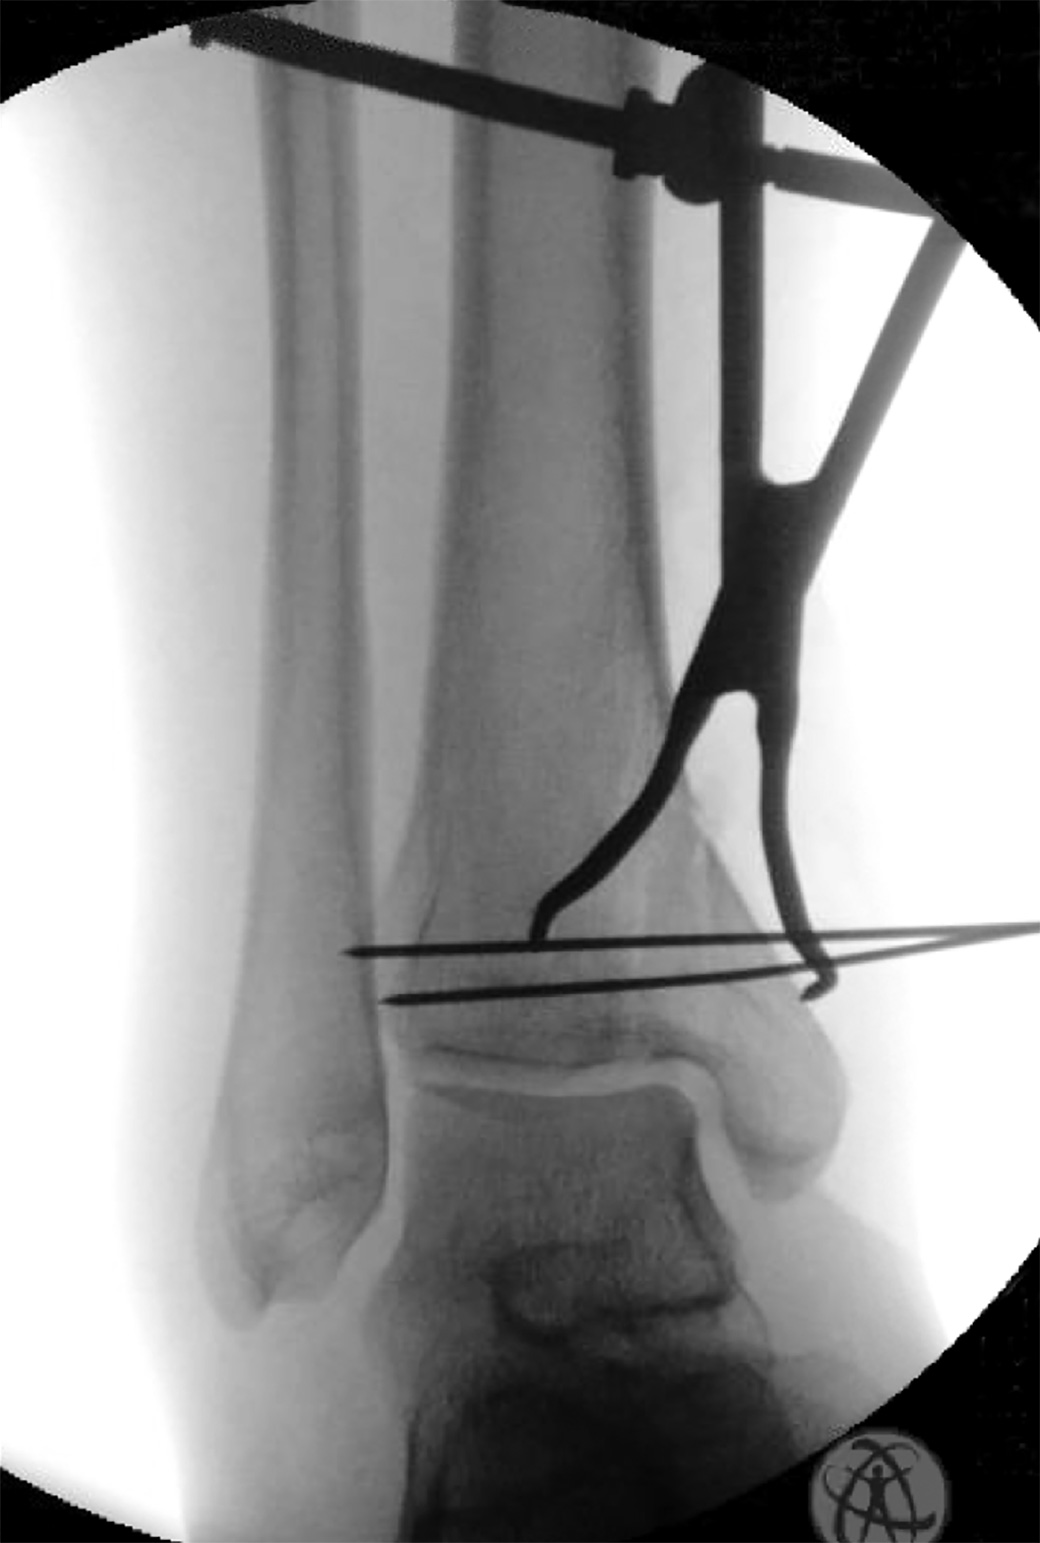

Versatile set of fracture reduction clamps, each with a specific tine design that allows for appropriate vector placement so that anatomic reduction can be obtained in a number of different types of fractures

• 1.9 mm tines allow for a snug fit in 2 mm drill holes

• Tines angled to prevent clamp “slippage” with compression

• Straight tines can be placed deep within bone which allows for far cortex compression.

• Example applications: any transverse fracture (straight-straight clamp), both bone forearm fractures, olecranon fractures, medial malleolus fractures, and many more.